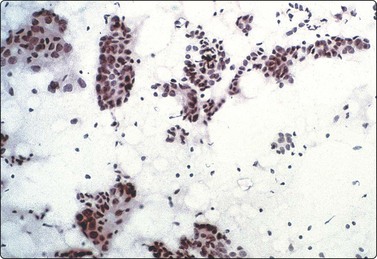

image image

Fig. 7.1 Radiation-induced atypia

(A) The epithelial cells in this irregular cluster show considerable nuclear enlargement, pleomorphism and hyperchromasia, but also some degenerative changes such as loss of nuclear structure (MGG, HP); (B) Corresponding tissue section (H&E, IP).